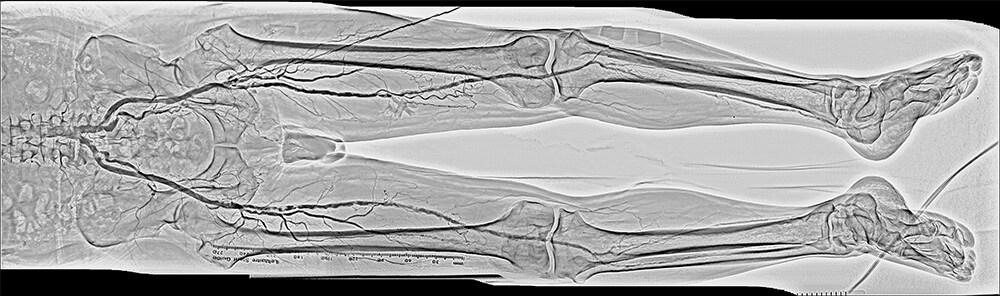

Real-time whole peripheral observation, "SCORE Chase"*

Shimadzu SCORE Chase enables freely panning longitudinally or laterally during exposures to trace blood flow through blood vessels.

After exposure, SCORE Chase instantly creates a positionally-corrected stitched image automatically and displays it on the monitor so that the overall blood flow through blood vessels in the lower extremities can be determined easily.